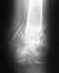

В июне была сделана операция по тотальному эндопротезированию тазобедренного сустава, после травмы.

Операцию проводили в г. Херсон (Украина), т.к. другого места ближе не было. Все прошло успешно (как сказали там). Очень сильно болела тазовая связка. В начале сентября вернулись домой (г. Иркутск).После консультации в институте ортопедии сказали, что протез поставлен на 1 см выше. Никакой реабилитации не было. С 8 сентября больничный закрыл, т.к. чувствовал себя отлично.Числа с 2 октября хожу без тросточки. В местной поликлинике стал ходить на лечебную физкультуру и массаж. И вот два дня назад стало болеть колено. Эта боль с удвоенной силой отдает по всей ноге. Ходить без костылей не возможно, точнее и с костылями тяжело. Любое движение отдает нестерпимой болью. Не знаю с чем это связано, и что можно предпринять. Купили обезболивающее "Кетонал" (ставили, когда лежал после операции), боль снижается но не совсем.Помогите, пожалуйста, не знаю что делать. Местные врачи ничего не могут подсказать. ПОЖАЛУЙСТА